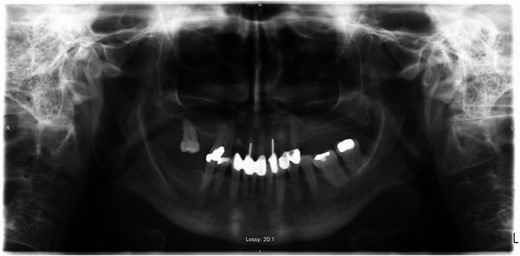

A 69-year-old female with a history of bilateral total hip replacements presented with rigors, fever and sudden onset left groin pain. A pelvic X-ray showed well-fixed implants. Blood results revealed a leucocytosis (white cell count 22.3 × 109 l–1) and elevated C-reactive protein (211 mg/l). Ultrasound-guided aspiration of her left hip grew Streptococcus gordonii. No source infection could be identified apart from a new chronic sinus infection in a left upper incisor. Following a discussion with the patient a 6-week course of intravenous ceftriaxone was started and was successful in normalizing her inflammatory markers. She was placed on long-term suppressive amoxicillin following this. Her suppressive antibiotic therapy was complicated by the development of a clostridium difficile infection and her antibiotics were changed to doxycycline. At 1-year follow-up, she was asymptomatic with no further episodes of groin pain or fever.

Prosthetic joint infection (PJI) following total hip replacement (THR) occurs in 1–2% of procedures but is one of the primary reasons for prosthesis revision (1). We report the only case of Streptococcus gordonii, a member of the viridans group streptococci (VGS), causing PJI in the setting of THR.

PJI occurs via direct inoculation, contiguous or haematogenous spread. Late onset infections (>12 months after surgery) are predominantly due to haematogenous seeding of virulent pathogens at another site (urinary tract, soft tissue infection). PJI is primarily caused by staphylococci with only a small percentage caused by streptococci, <10% [1, 2]. Streptococcus gordonii, a member of the Streptococcus Sanguinis group, a subdivision of VGS, is one of the microbiota of the oral cavity that contributes to plaque formation. It is recognized in the setting of bacterial endocarditis [3], but has only recently been described in the literature as causing PJI, in the setting of total knee replacement reported in 2015 [4].